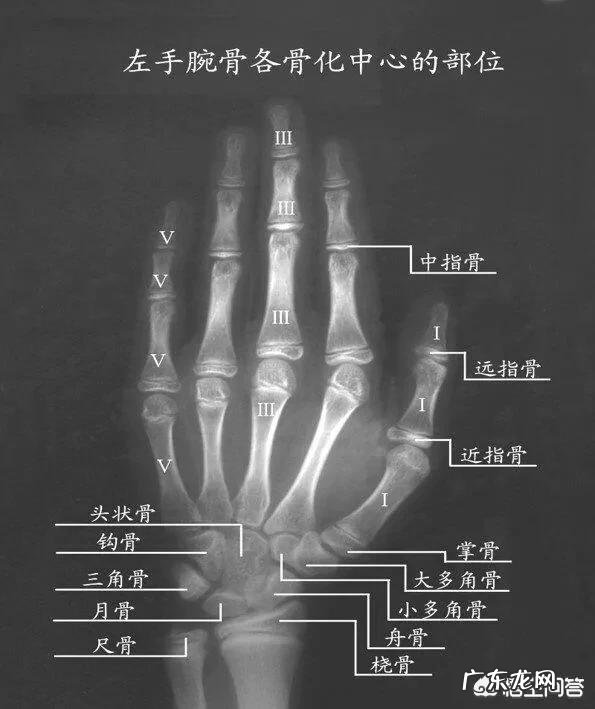

许多家长也会问,测骨龄要去省会城市不方便,当地没有懂骨龄与性早熟的医生 。我告诉大家一个办法,先去任何一家医院,不管大小拍摄一张孩子左手手掌骨龄片(许多医院骨科医生也不懂的话出示标准片看就会明白,不用拍膝盖,要拍全包括29块骨,如果家长不懂什么叫标准骨龄片可以关注我留信我发一张标准左手骨龄片样片给你) 。去淘宝淘一下(骨龄检测)服务,许多专业骨龄医生利用互联网开了店铺,服务态度很好,可以读片分析咨询建议,很方便 。